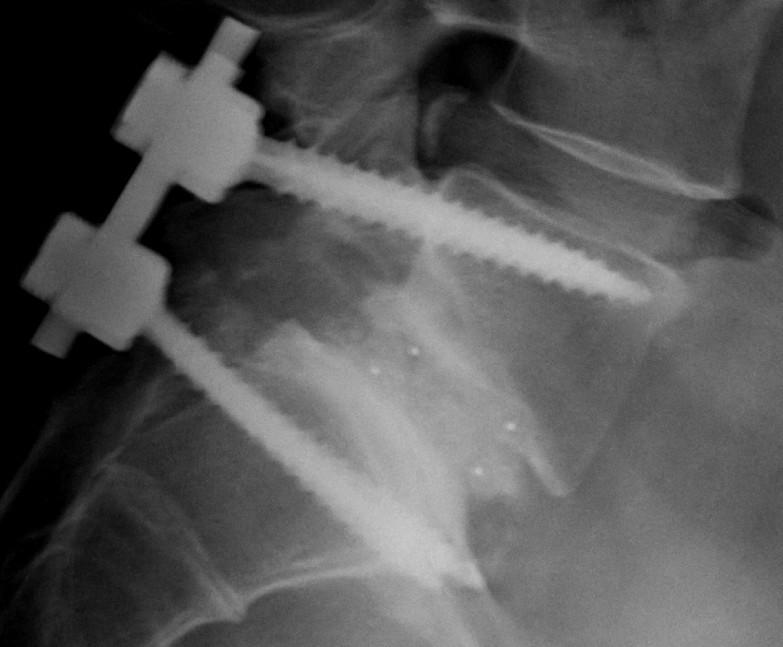

MIS Pedicle Screw (Scoliosis Correction / Spinal Fusion)